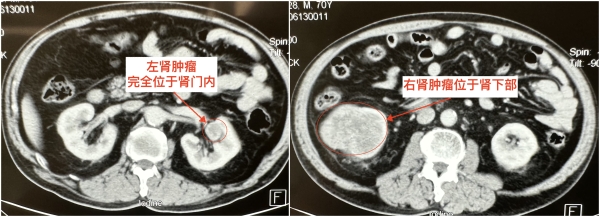

2023年6月15日,患者任某检查发现两侧肾脏均有不明肿块,右侧肿块位于肾下级,大小8cm×7cm×5cm,左侧肿块位于肾门内,大小2.5cm×2cm×2cm,并被肾实质完全覆盖。这对于一位70岁的老人来说犹如晴天霹雳,家里人也十分着急,辗转多家医院均被告知保留肾脏手术难度大,术后可能需要依靠透析生存。后患者经多方打听,了解到西安交大二附院泌尿外科治疗肾癌临床经验丰富,遂经种铁主任门诊收住入院。

患者入院后由肾肿瘤专业组付德来副主任医师、唐骁爽主治医师具体负责,经完善相关检查,科室术前讨论一致认为患者双侧肾癌诊断明确,有手术适应征,无手术禁忌征,建议积极手术治疗,手术方式首选保留肾功能的肾部分切除术。种铁教授为患者仔细分析病情,患者右侧肾癌占据右肾整个下半部,需行半肾切除,术中需严格执行无瘤原则,完整切除肿瘤,并严密缝合止血。左侧肾癌完全位于肾窦内,位置刁钻,与肾动静脉、肾盂肾盏关系密切,术中需轻柔操作,在切除肿瘤的同时避免副损伤。我院引进的最新一代达芬奇手术机器人在血管解剖、肿瘤切除及组织重建方面具有明显优势,可尽可能缩短肾脏缺血时间,最大限度保护肾脏功能,建议行机器人辅助腹腔镜双侧肾部分切除术。